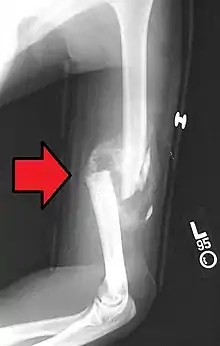

A transverse fracture of the humerus shaft

A spiral fracture of the distal one-third of the humerus shaft

A displaced supracondylar fracture in a child